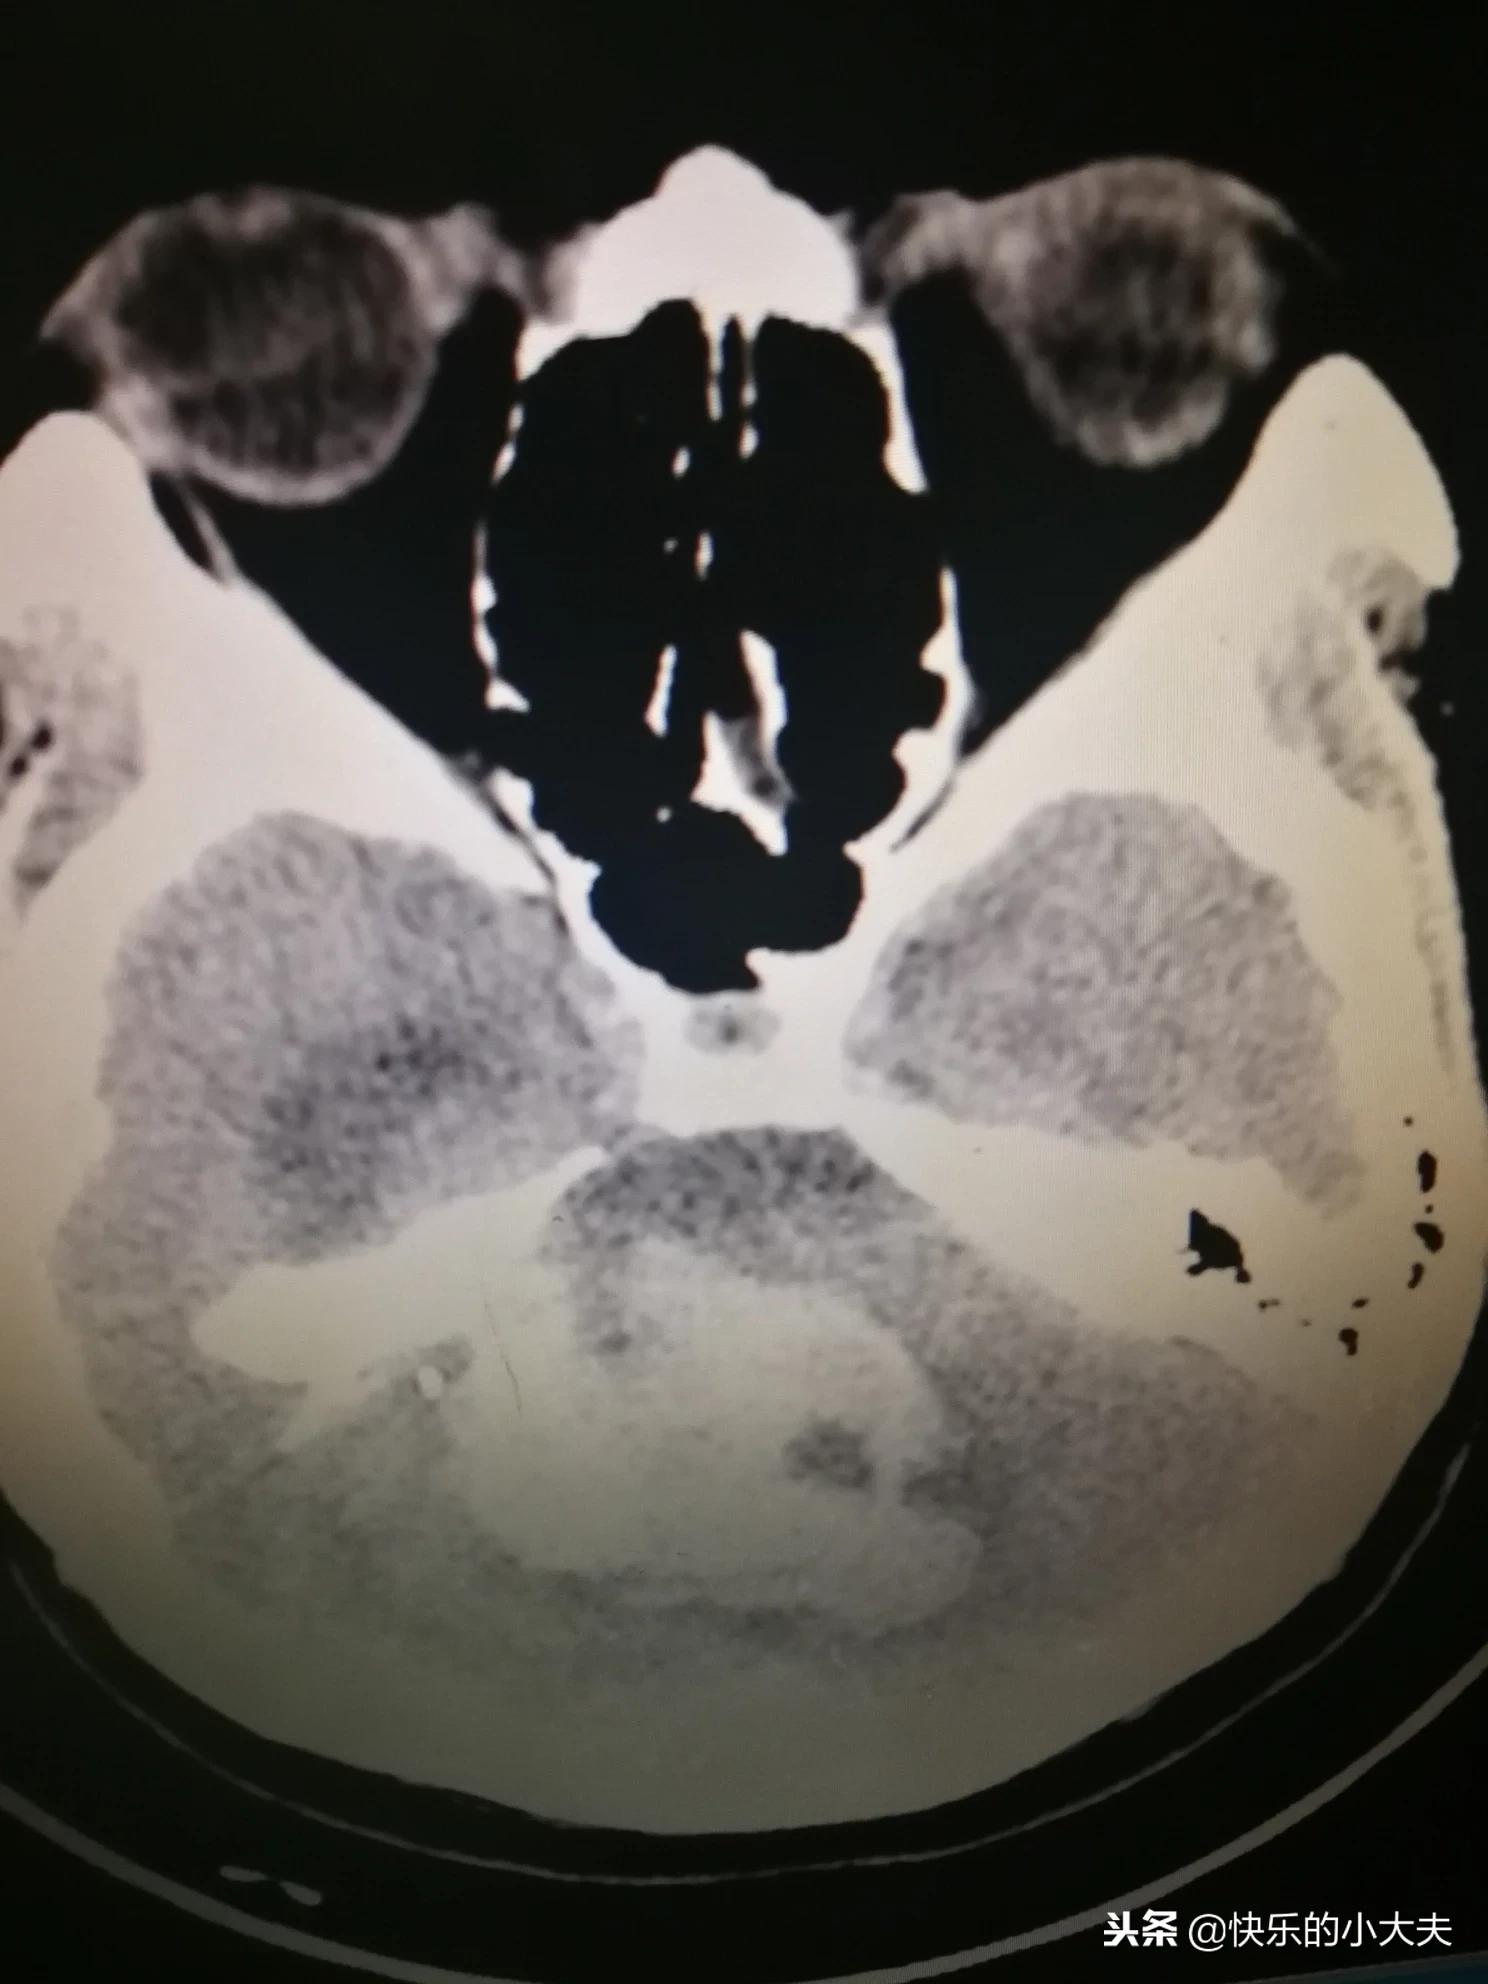

有一个患者在家突发昏迷,送到医院确诊为大量的脑干出血,和家属说患者活的几率不大。

听到实情的一个家属也立刻晕倒了,医生赶紧把家属也推进ICU里抢救,家属慢慢的清醒,赶紧也做了个CT,没有明显的病灶,并且活动意识都恢复了。